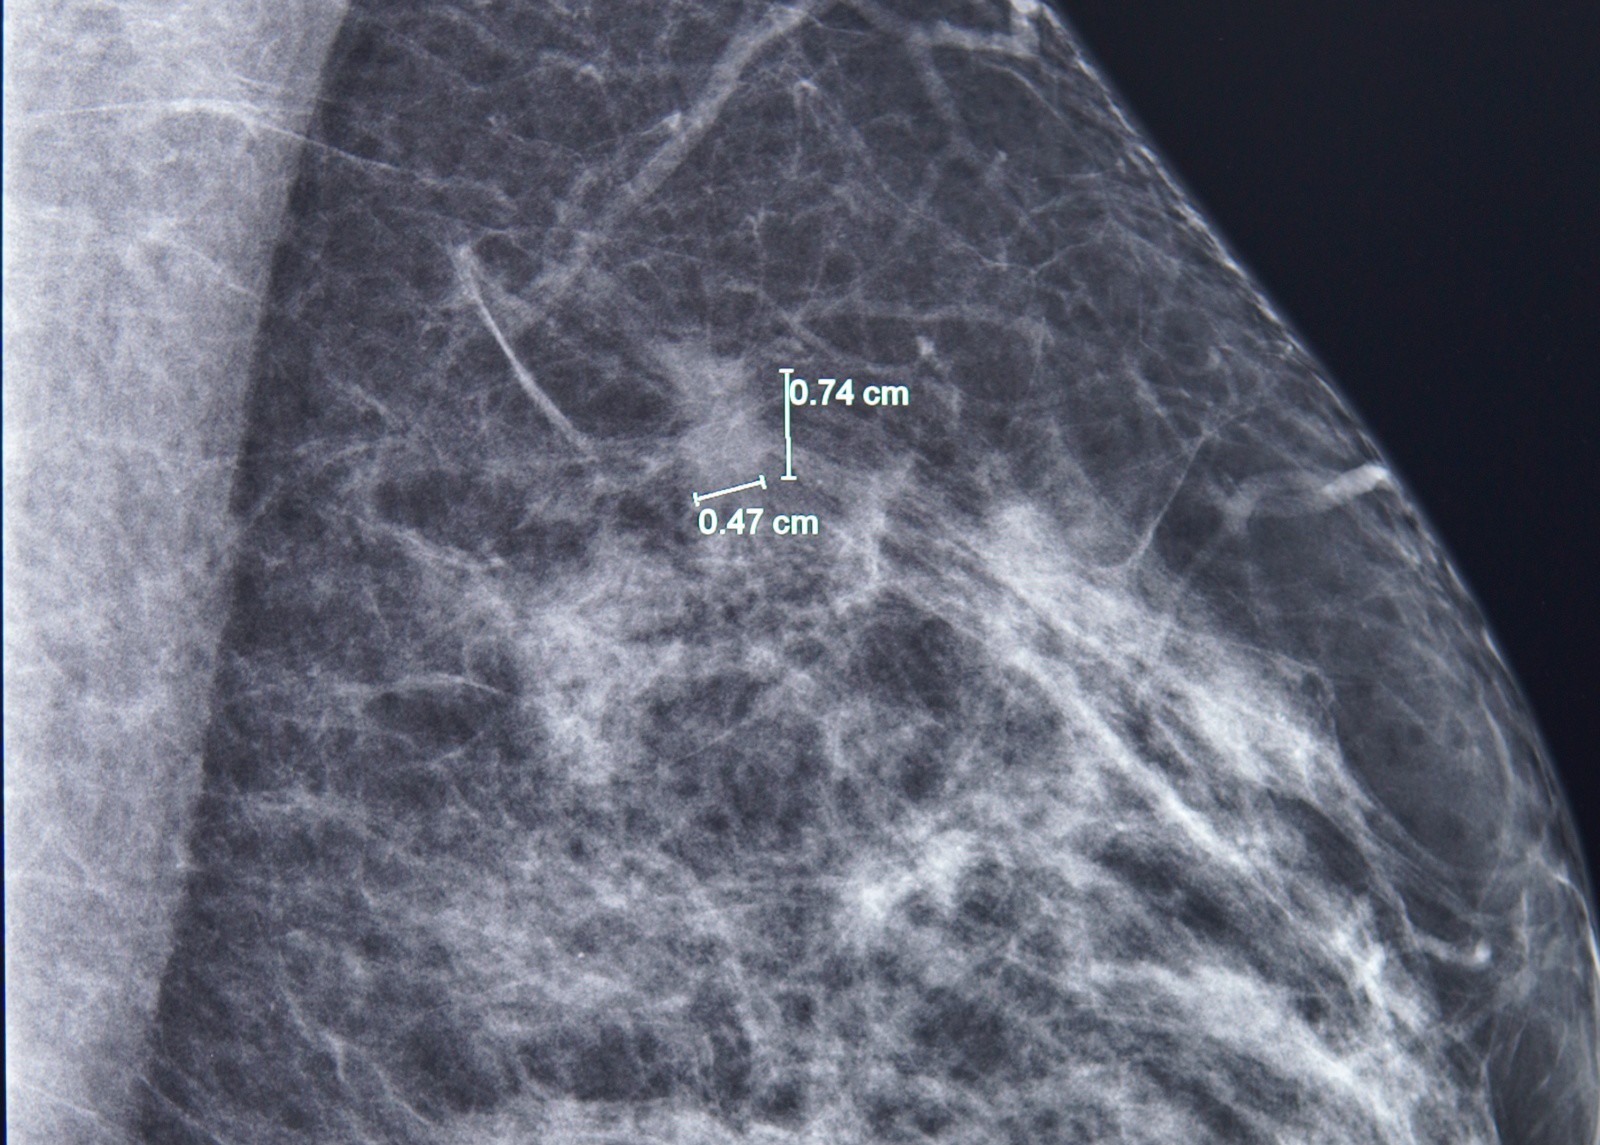

Kết quả nhũ ảnh tìm ra một tổn thương nhỏ, khoảng 7mm ở vú trái. BS.CKI Phùng Ngọc Thư – Trưởng Trung tâm Chăm sóc Tuyến vú FV cho bệnh nhân chụp thêm cộng hưởng từ (MRI) do mô vú của bà A. khá đặc. Qua phim chụp MRI, bác sĩ Thư đã phát hiện thêm một nốt tổn thương khác, chỉ 3mm.

Phát hiện một tổn thương 7mm ở vú trái bằng chụp nhũ ảnh. Ảnh: FV